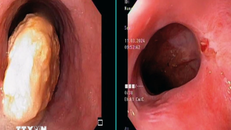

Bé trai nhập viện sau 2 ngày đau bụng. Qua nội soi, bác sĩ ghi nhận bé bị thủng ruột nhiều nơi do 8 thanh nam châm ở các quai ruột khác nhau hít lại với nhau, tì đè lên thành ruột.